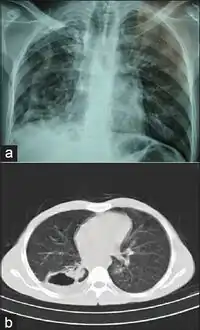

The first strains of M. branderi were isolated from samples obtained from nine patients, some of whom had cavitary mycobacteriosis of the lungs that was resistant to available drugs. In most cases, repeat samples obtained from each patient were positive for acid-fast bacilli as determined by microscopy, and the only cultivable species was M. branderi. M. branderi has to be considered a potential human pathogen.